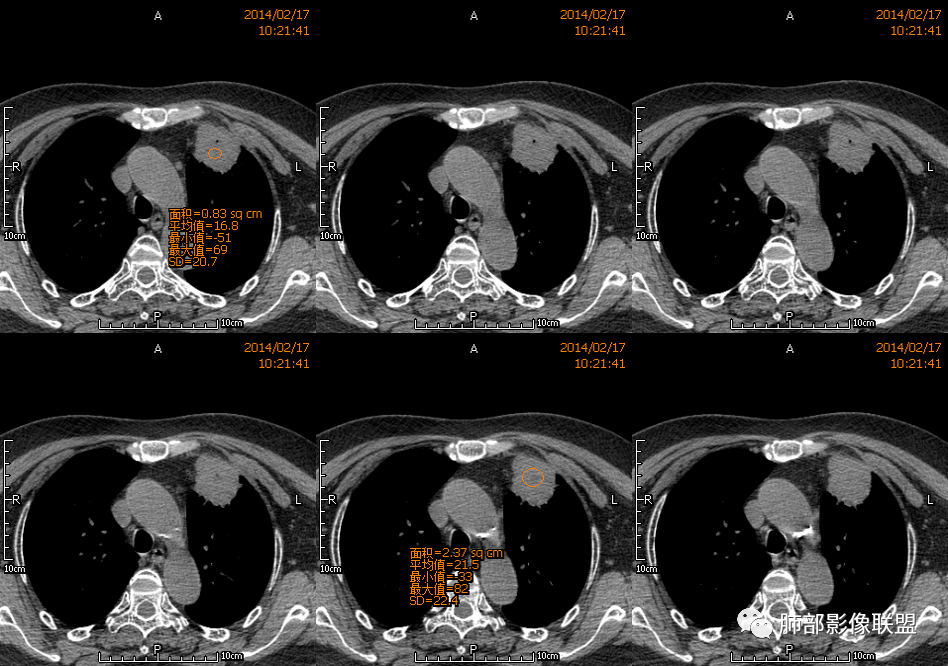

水晶石头: 患者老年女性,咳嗽咳痰10天,痰中带血4天余。查血常规白细胞低;肿瘤标志物、凝血功能正常;血生化:蛋白低;C反应蛋白、血沉稍升高。胸部CT:左肺上叶前段胸膜下沿气管支气管走形肿块影,长轴与胸膜平行,见分叶、毛刺、支气管截断、空泡征象。增强明显强化,且见血管造影征及病灶内小灶低密度坏死区。左肺上叶尖后段见一结节灶。综合考虑恶性病变可能大,腺癌或淋巴瘤可能。鉴别诊断肺脓肿。

3.病灶密度不均,中央坏死液化并见气泡影,支气管及血管贴边进入,较均匀环形强化(显示多层结构),未见明确壁结节。

1.块影不规则,未见分叶、毛刺及张力,未见壁结节,肺门纵隔未见肿大淋巴结等,缺少肺腺癌的特征。

3.病灶易坏死液化,环形强化,支气管及血管贴边进入,“火焰”样边缘轮廓,更符合炎性块影的特点。